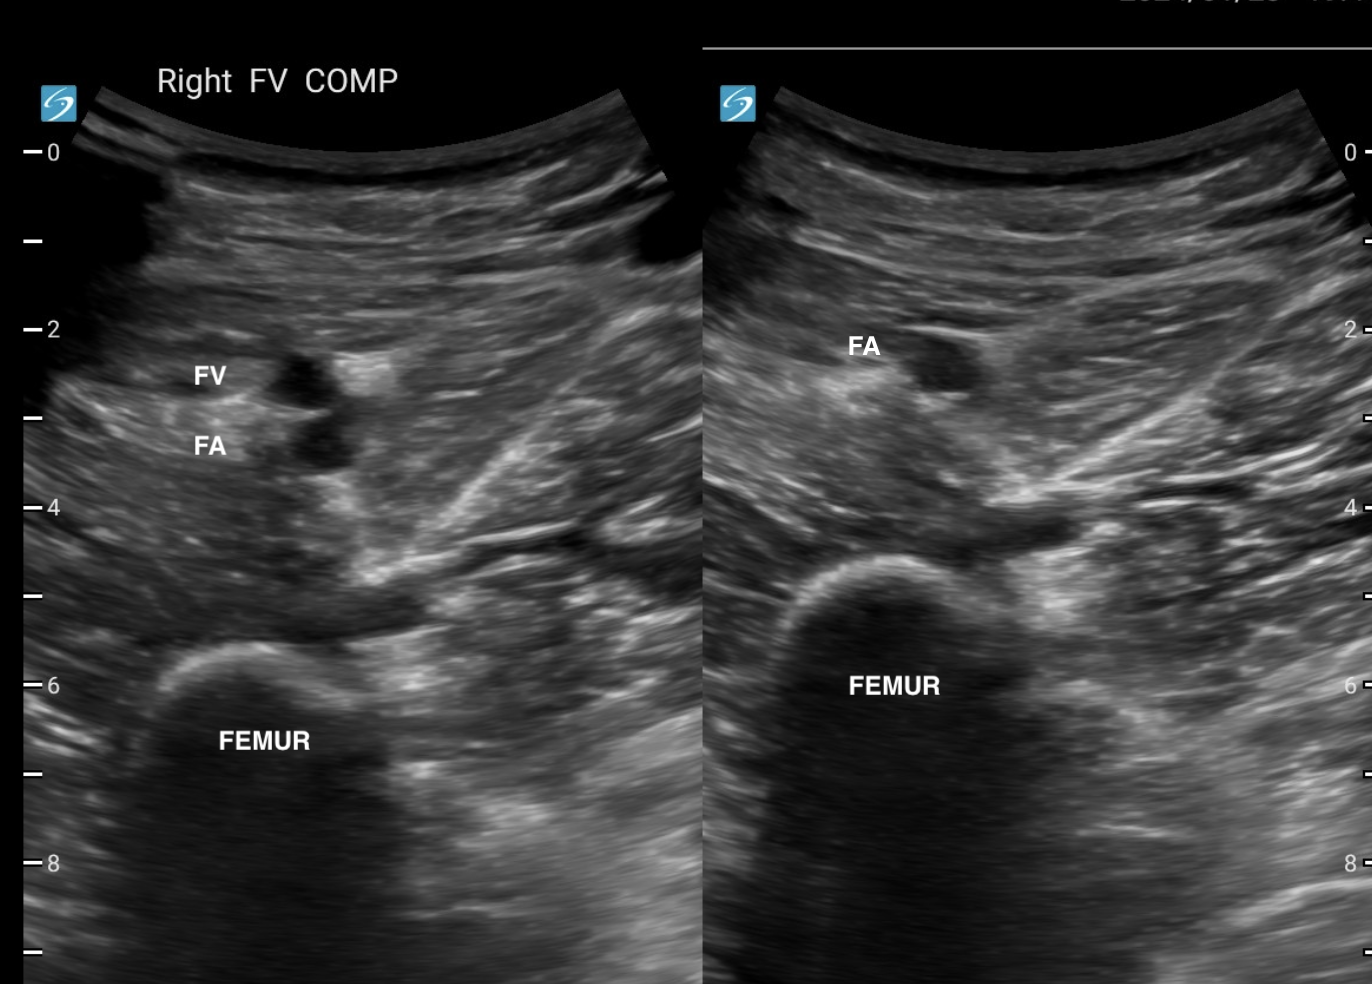

FEMORAL VEIN

The femoral vein travels medially down the leg and passes under the sartorius muscle at the adductor canal. Mostly it can be compressed with downward pressure. At the adductor canal, have the probe facing the medial femur and compress the vein against the femer by putting lateral pressure. At this point, you may need to help with medial pressure from your hand against the patient's lateral leg.

pressure against the medial femur at the adductor canal